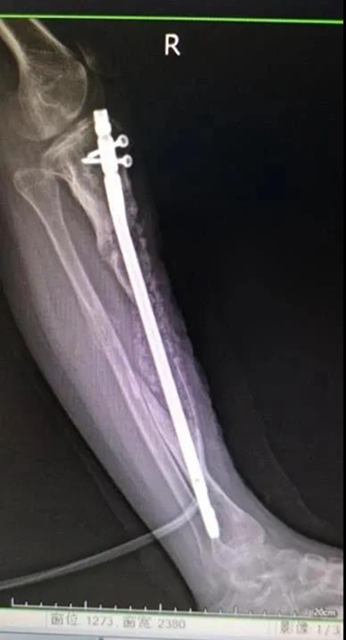

邹永根教授立即为朗朗进行了仔细检查,发现朗朗左腿短、小、细,比右腿短了足足15厘米。

“朗朗病程长,病情复杂,胫骨骨髓炎伴随胫骨缺损,治疗难度极大。”经过全科室讨论,骨伤科(矫形·儿骨·手外组)团队为朗朗制订了治疗方案——Ilizarov骨搬运技术:

第一步:切除感染的骨头,治好骨髓炎;

第二步:应用外固定支架延长肢体;

第三步:自体骨植骨修复骨缺损。

经过两年的治疗周期,双腿终于一样长了,自体骨移植成功!

邹永根教授介绍:Ilizarov骨搬运技术主要由钢针及环行外固定支架组成,可促进骨的再生与塑形。通过牵拉成骨对活体组织持续、稳定的缓慢牵拉,刺激或激活某些组织细胞的再生,并逐渐形成骨小梁,最后骨化。